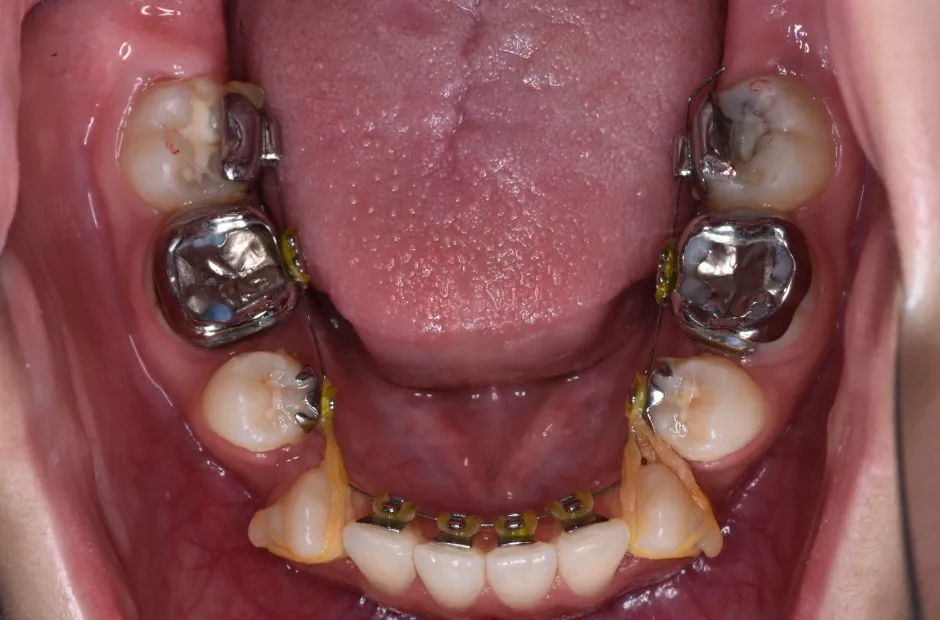

先天欠如

| 診断名・主訴 | 先天欠如 |

|---|---|

| 年齢・性別 | 14歳・女性 |

| 治療期間・回数 | 2年 |

| 治療に用いた主な装置 | ブラケット矯正 |

| 抜歯部位 | なし |

| 治療費 | 60万円(税抜) |

| リスク・副作用 | 装置による違和感・疼痛・歯肉退縮・歯根吸収・虫歯のリスクなど |

治療前

治療中

治療後